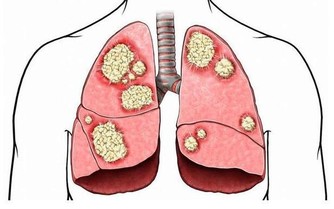

❶、【功能與主治】:滋補肝腎,益精明目。用於虛勞精虧,腰膝痠痛,眩暈耳鳴,內熱消渴,血虛萎黃,目昏不明。 4黃芪

廣告 - 請繼續往下閱讀 ❶、【功能與主治】:補氣固表,利尿托毒,排膿,斂瘡生肌。用於氣虛乏力,食少便溏,中氣下陷,久瀉脫肛,便血崩漏,表虛自汗,氣虛水腫,癰疽難潰,久潰不斂,血虛痿黃,內熱消渴;慢性腎炎蛋白尿,糖尿病。蜜製黃芪益氣補中。用於氣虛乏力,食少便溏。 5山楂